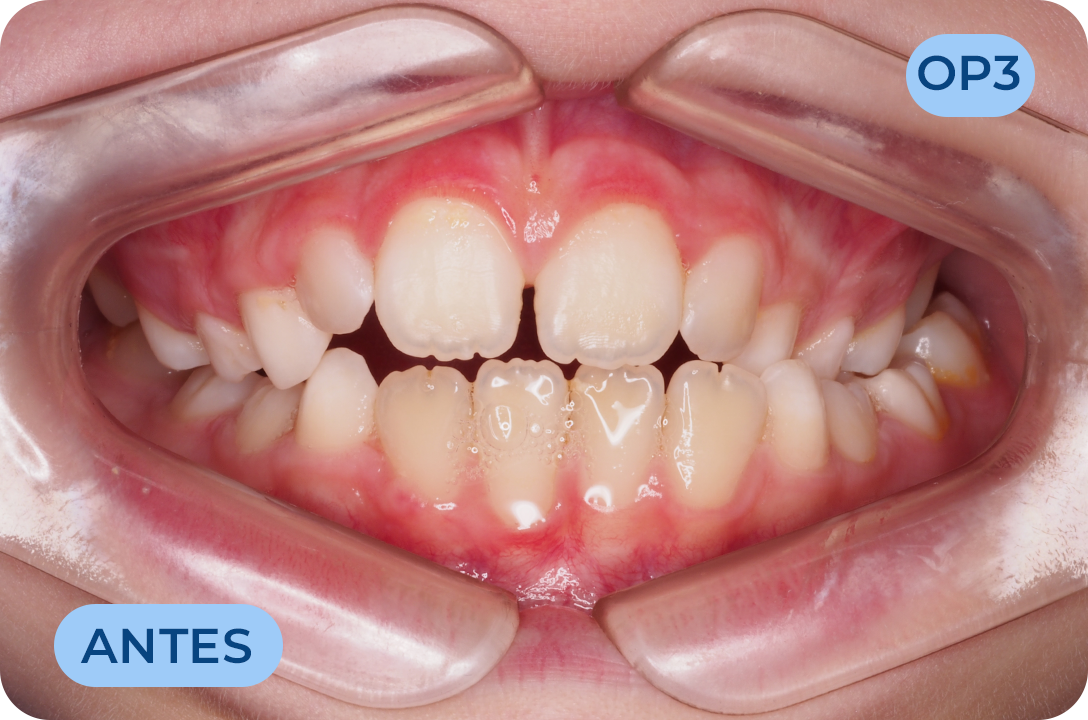

Ortodontia

É a especialidade da Medicina Dentária que se debruça sobre o estudo e correção das más posições dentárias e dos maxilares. Atualmente é possível tratar pacientes de todas as idades, no entanto a 1ª consulta deve ser realizada ainda na infância para intercetar eventuais problemas de desenvolvimento esquelético e funcional.